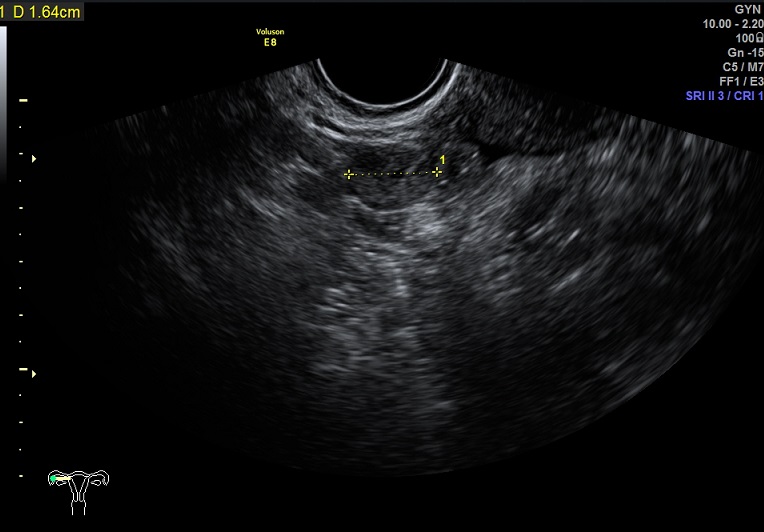

2015-1-12,月经第3天检查

左卵巢: 大小2.9x2.3x1.4cm 体积:4.8 窦卵泡:4个 卵巢间质血流:9.8cm/s RI:0.49

右卵巢: 大小 2.6x1.6x1.3cm 体积:2.8 窦卵泡:2个 卵巢间质血流:11.5cm/s RI:0.52